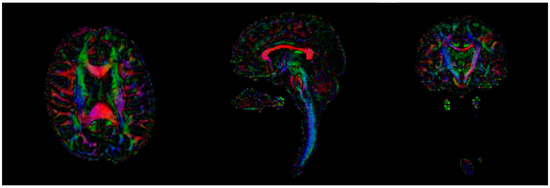

2.1.1. Image Processing

2.1.2. Connectomics

- Baliyan, V.; Das, C.J.; Sharma, R.; Gupta, A.K. Diffusion weighted imaging: Technique and applications. World J. Radiol. 2016, 28, 785–798. [Google Scholar] [CrossRef] [PubMed]

- Mori, S.; Zhang, J. Principles of Diffusion Tensor Imaging and Its Applications to Basic Neuroscience Research. Neuron 2006, 51, 527–539. [Google Scholar] [CrossRef] [PubMed]

- Romero, C.; Ghisi, J.P.; Mazzucco, J.; Ternak, A. Imágenes con tensor de difusión en resonancia magnética. Rev. Argent. Neuroc. 2007, 21, 4499. [Google Scholar]

- Jones, D.K. Studying connections in the living human brain with diffusion MRI. Cortex 2008, 44, 936–952. [Google Scholar] [CrossRef]